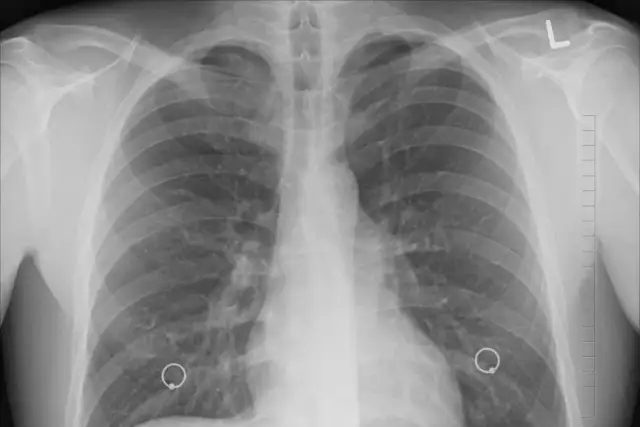

Badania dodatkowe: Kiedy konieczne jest RTG klatki piersiowej lub badanie krwi?

W niektórych sytuacjach, aby postawić trafną diagnozę, lekarz może zlecić dodatkowe badania. Na przykład, przy podejrzeniu zapalenia płuc, zwłaszcza jeśli osłuchowo słychać zmiany lub dziecko ma uporczywą gorączkę i duszności, konieczne może być wykonanie RTG klatki piersiowej. Badanie krwi, w tym morfologia z rozmazem i parametry stanu zapalnego (np. CRP), może pomóc w ocenie, czy mamy do czynienia z infekcją wirusową, czy też doszło do nadkażenia bakteryjnego. Czasami, w przypadku nawracających problemów z uchem, lekarz może skierować na konsultację laryngologiczną.